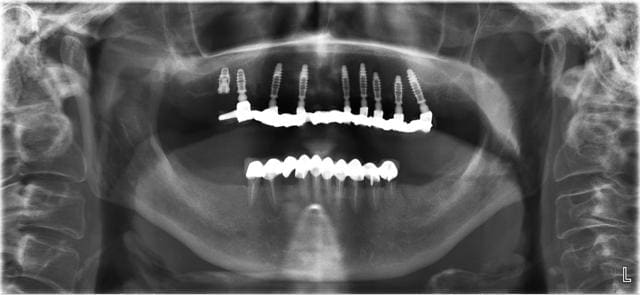

Pas mal............ et sans vis savourez nonolien c'est une première Mondiale ! J'entends: sans AUCUNE vis.

Un peu trop de taf pour soutenir la discussion. Je vous met la pano à 8 jours.